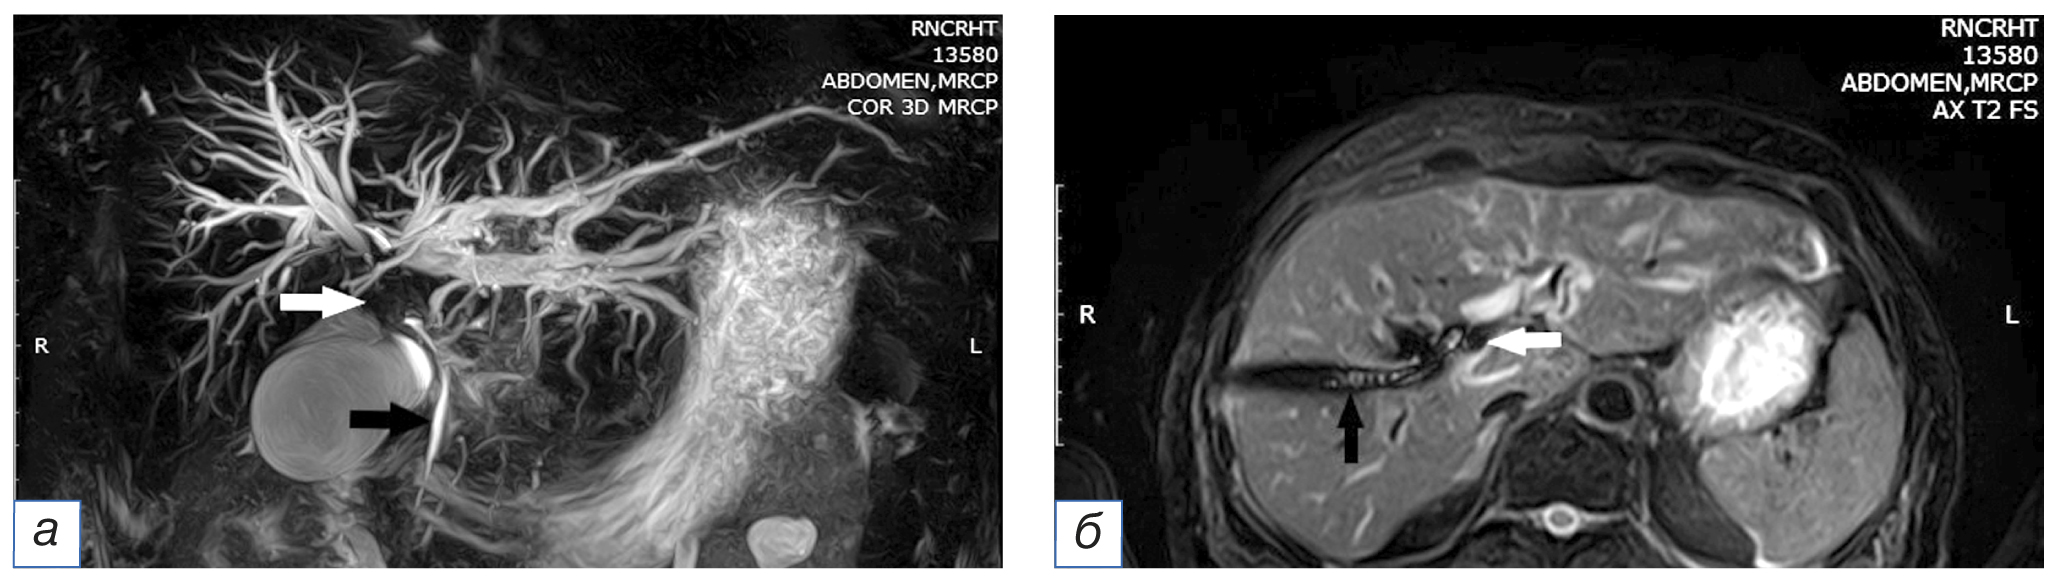

Рис. 1. Ангиограммы пациента с опухолью Клацкина, Bismuth IV: а — селективная ангиография общей печеночной артерии катетером cobra (определяется узурация ветвей левой печеночной артерии, белая стрелка); в проекции желчных протоков визуализируется наружно-внутренний холангиодренаж (черная стрелка); б — возвратная портомезентерикография (сдавление опухолью ствола воротной вены, стрелка).

Fig. 1. Patient with Klatskin tumor, Bismuth IV, angiography: а — common hepatic artery selective angiography with a cobra catheter (usuration of the branches of the left hepatic artery were determined, white arrow); in the projection of the bile ducts, external-internal cholangiodrainage is visualized (black arrow); б — recurrent portomesentericography (tumor compression of the portal vein, arrow).

Рис. 2. Тот же больной через 2 мес. Магнитно-резонансная томография, совмещенная с холангиографией: визуализируются расширенные протоки левой доли печени: а, б — опухоль желчных протоков (белая стрелка), холангиодренаж, установленный через правую долю печени (черная стрелка).

Fig. 2. The same patient after 2 months. Magnetic resonance imaging imaging combined with cholangiography: dilatated duct of the liver left lobe are visualized: а, б — biliary ducts tumor (white arrow), cholangiodrainage passed through the right lobe of the liver (black arrow).